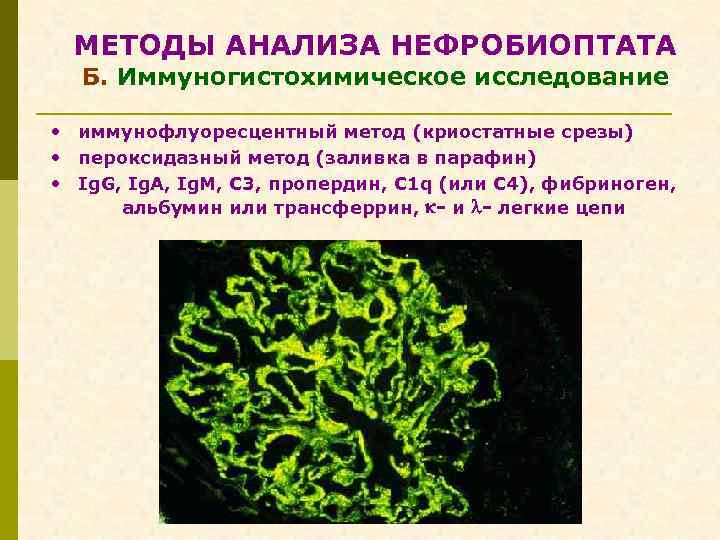

МЕТОДЫ АНАЛИЗА НЕФРОБИОПТАТА Б. Иммуногистохимическое исследование • иммунофлуоресцентный метод (криостатные срезы) • пероксидазный метод (заливка в парафин) • Ig. G, Ig. A, Ig. M, C 3, пропердин, C 1 q (или C 4), фибриноген, альбумин или трансферрин, - и - легкие цепи